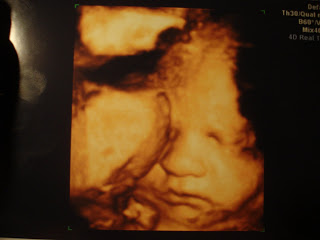

(The pictures are a lot better quality in original form, but I had to take a picture of a picture with our camera since we don’t have a scanner.)

Our little chubby-cheeked baby! (Ultrasound in 3D color)